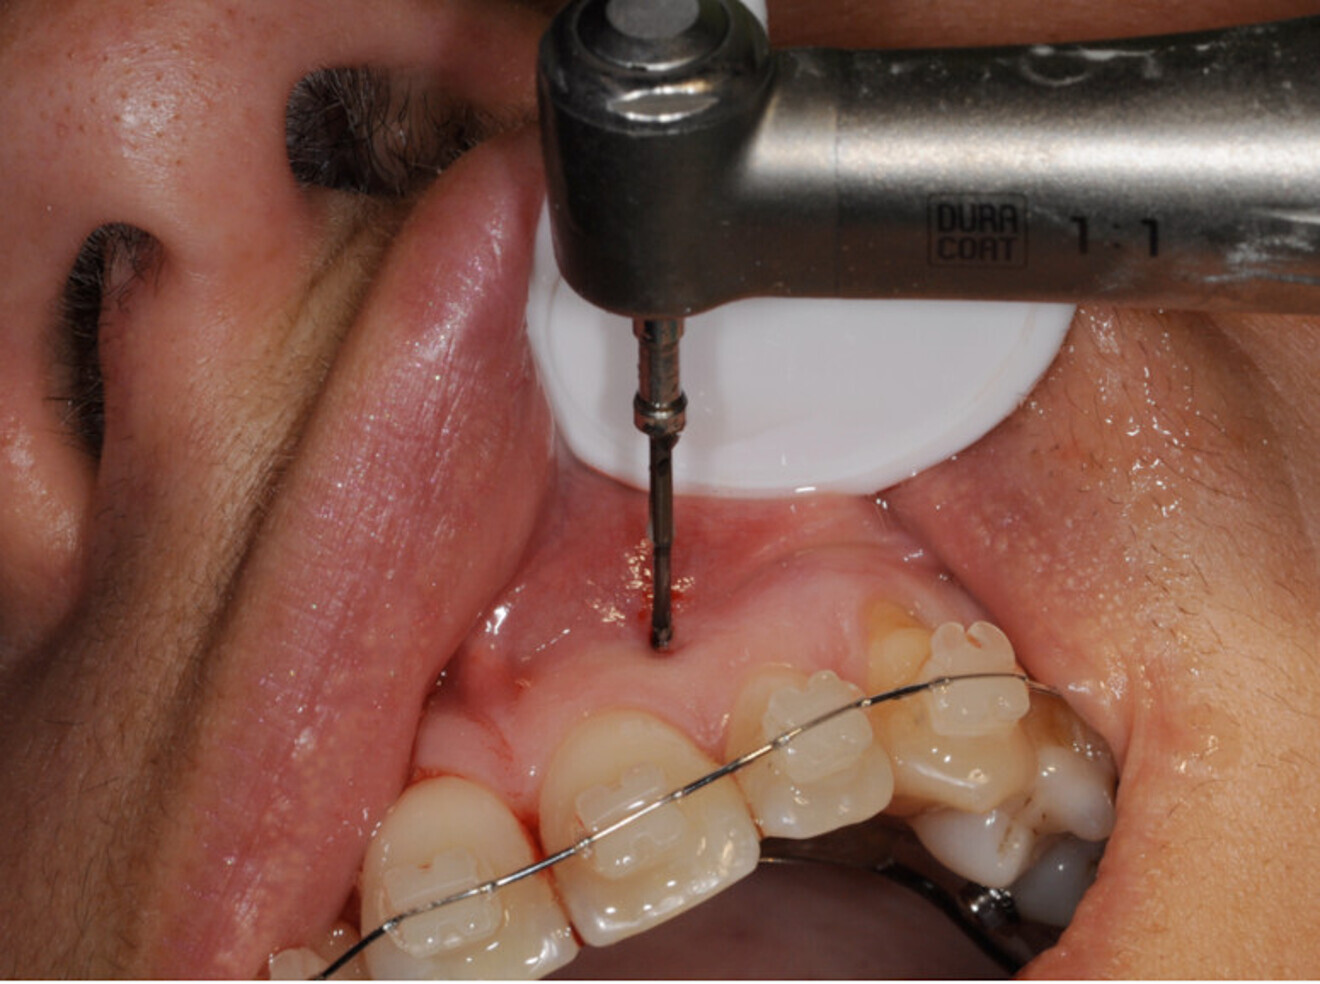

Il s’agit à présent d’instruments manuels et rotatifs. Ils sont réalisés en acier inox recouvert d’une couche de carbone diamant, et présentent une pointe très effilée afin de pénétrer l’os facilement.

L’énorme avantage des ostéotenseurs est le fait de pouvoir les utiliser à ciel fermé, ce qui évite de devoir lever un lambeau mucopériosté, et donc de priver la corticale osseuse de son irrigation.

On commencera ensuite à tester avec les instruments manuels la densité de la corticale osseuse.

Si la densité est faible et que la corticale est aisément passée, on n’utilisera que les instruments manuels. Au contraire face à une corticale dure ou à un os dense, on utilisera les instruments rotatifs sur CA à 20 000 t/min sous irrigation. Pour ces instruments rotatifs, il faut disposer sur l’instrument une butée active, afin d’éviter de léser des structures anatomiques comme le nerf dentaire inférieur.

On pratique une série de piquages de 4 à 6 mm sur le sommet de la crête alvéolaire édentée, une deuxième du côté lingual ou palatin, et une troisième du côté vestibulaire à une distance de la crête comprise entre 4 et 8 mm.